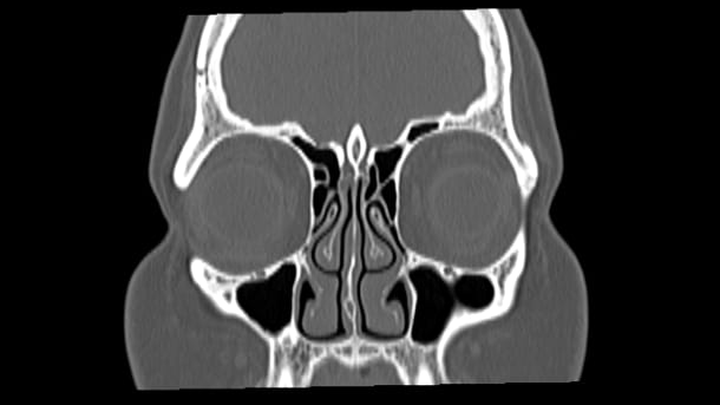

En los últimos meses, Jas comenzó a presentar un síntoma alarmante: fuga de líquido cefalorraquídeo a través de las fosas nasales, causada por una fisura en el tejido cerebral y presión craneal elevada. Tras semanas de estudios, consultas con especialistas y un proceso de diagnóstico que no ha sido fácil, Jas fue sometida a una cirugía para corregir la fuga.

Durante este proceso, los médicos también le diagnosticaron Síndrome de la Silla Turca Vacía, una condición que requiere atención neuroendocrinológica continua.